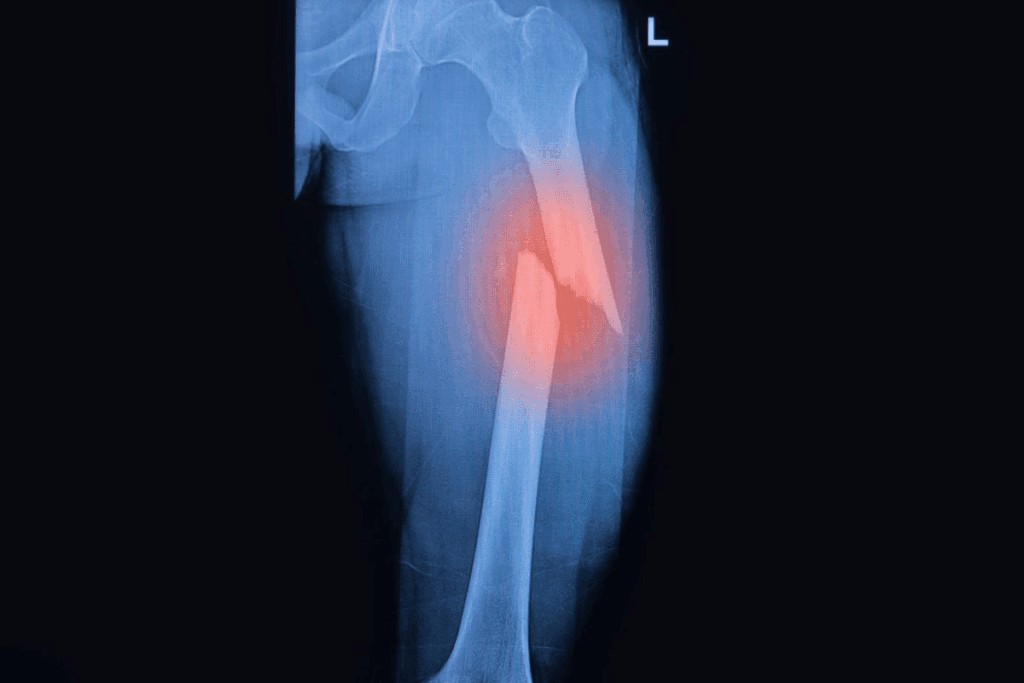

Imaging Methods Used

Imaging is key in diagnosing bone fractures. The main imaging tools are:

- X-rays: The first choice for seeing bone fractures clearly.

- CT scans: Good for complex fractures or when X-rays aren’t clear enough.

- MRI Page involve a combination: Helps check soft tissue injuries with fractures.